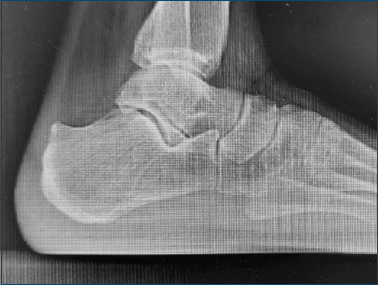

Figura 1. Radiografia che mostra la deformità postero-superiore del calcagno, tipica della malattia di Haglund.

La malattia di Haglund consiste in una prominenza postero superiore della grande tuberosità calcaneare, che fu descritta per la prima volta da Patrick Haglund nel 1928 come borsite retrocalcaneare in presenza di una protuberanza anomala del profilo postero-superiore del calcagno (Fig. 1). Questa fu inizialmente individuata in soggetti di fascia sociale elevata, che utilizzavano scarpe da golf, con un contorno posteriore rigido 1.